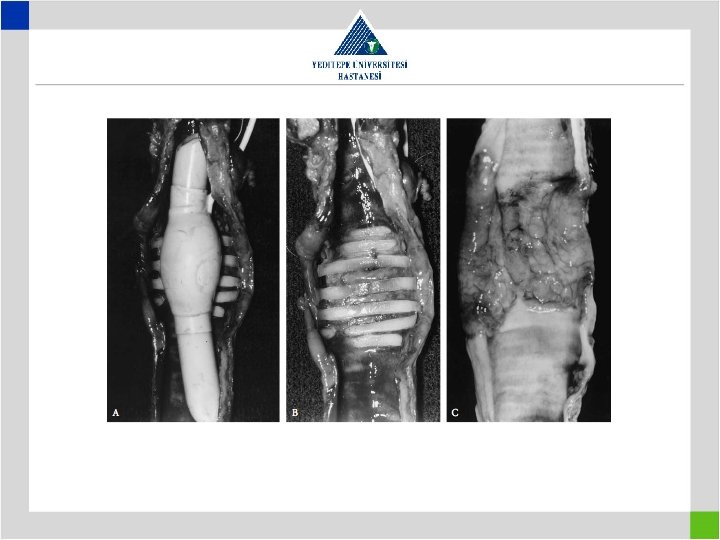

Iatrogenic Factors • Continuous suturing technique with nonabsorbable suture material resulting in restenosis

• Suture material preference – Nonabsorbable sutures • More calcification in anastomosis • Protruding into the lumen over time, causing granulation – Absorbable sutures • Monofilament • Multifilament • Suture technique – Interrupted suture in pediatric patients • 4/0 sutures in adults and 5/0 in pediatrics